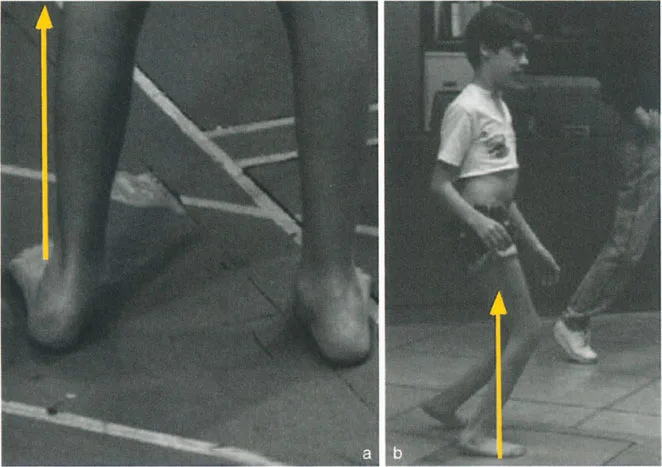

من الأمثلة السريرية الكلاسيكية للتشوه الديناميكي هو "حنف القدم الوظيفي" (Functional Equinus)، والذي يُرى غالبًا في حالات الشلل الدماغي أو التشنج بعد الإصابات. في وضع الفحص السريري الثابت، ومع ثني الركبة لإرخاء عضلة الساق (Gastrocnemius)، قد يكون المريض قادرًا تمامًا على ثني القدم ظهريًا بشكل سلبي (Dorsiflexion) لتتجاوز الوضع المحايد. ومع ذلك، أثناء مرحلة الوقوف على ساق واحدة في دورة المشي، تظل القدم في وضع حنف القدم المتيبس.

لماذا يحدث هذا؟ لأن الوقت المطلوب لتطبيق القوة العضلية للأعلى وثني القدم ظهريًا بنشاط يكون أكبر من المدة القصيرة لمرحلة الوقوف على ساق واحدة. غالبًا ما يتفاقم هذا بسبب التشنج الكامن، حيث تتغلب ردود الفعل الانعكاسية لوتر العرقوب (Achilles tendon) على العضلة الظنبوبية الأمامية (Anterior Tibialis).

- مشية حنف القدم (Equinus Gait): حيث تبقى القدم في وضع مدبب (Plantaflexion) أثناء المشي، مما يعيق حركة الكعب عن ملامسة الأرض بشكل طبيعي.